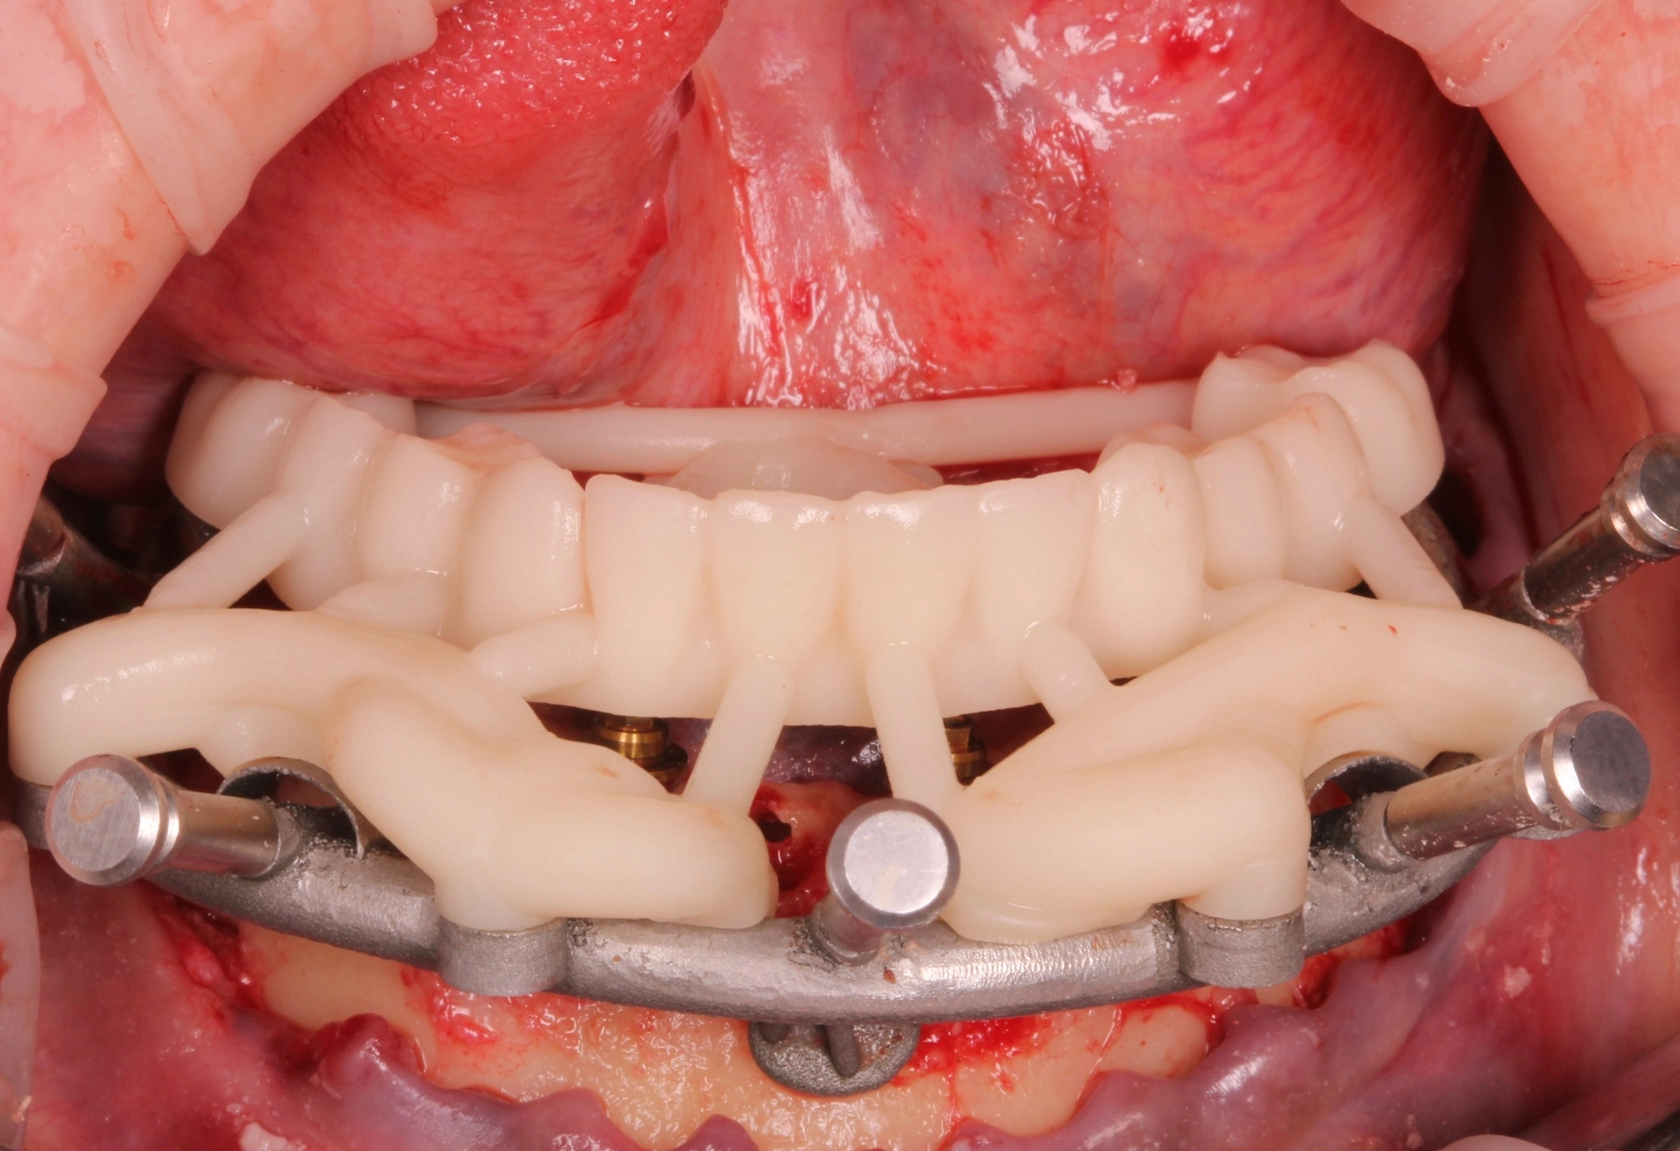

10. Возможность изготовления префабрикованных конструкций. - Готовые одиночные конструкции - Конструкции под вклейку/перебазировку - Сварка опорной титановой балки - Прототипы тотальных работ

Учебный проект 3 – моделирование разборного хир. Шаблона FP1

Моделирование шаблона для имплантации

Моделирование прототипа

Учебный проект 4 – моделирование разборного хир. Шаблона FP3